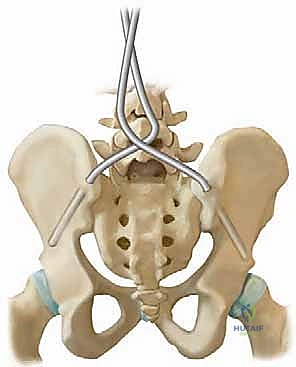

قضيب الوحدة هو غرسة معدنية طبية صلبة (مصنوعة عادة من الفولاذ المقاوم للصدأ أو التيتانيوم) تأخذ شكل حرف "U" المقلوب. يتم تشكيل هذا القضيب مسبقاً أو أثناء الجراحة ليتطابق مع الانحناءات الطبيعية المطلوبة للعمود الفقري (الحداب الصدري والقعس القطني).

1. التثبيت بالأسلاك (Sublaminar Wires): بدلاً من البراغي، يتم استخدام أسلاك معدنية مرنة وقوية تمرر بعناية فائقة تحت الصفيحة الفقرية (Lamina) لكل فقرة، ثم يتم ربطها وشدها حول قضيب الوحدة. هذا يوزع قوة التصحيح على مساحة واسعة من العمود الفقري، مما يقلل بشكل كبير من خطر كسر العظام أو فشل التثبيت.

2. تثبيت الحوض (Galveston Technique): يتم إدخال نهايتي حرف "U" (ساقي القضيب) عميقاً داخل عظام الحوض (الحرقفة - Ilium). هذا يربط العمود الفقري بالحوض ككتلة واحدة صلبة، مما يصحح ميلان الحوض فوراً ويسمح للطفل بالجلوس بشكل مستقيم.

6. التثبيت في الحوض (Pelvic Fixation)

يتم حفر مسارات دقيقة في عظام الحوض (Ilium). يتم إدخال نهايتي قضيب الوحدة في هذه المسارات بقوة وإحكام. هذه الخطوة هي سر نجاح استقرار جلوس الطفل مستقبلاً.